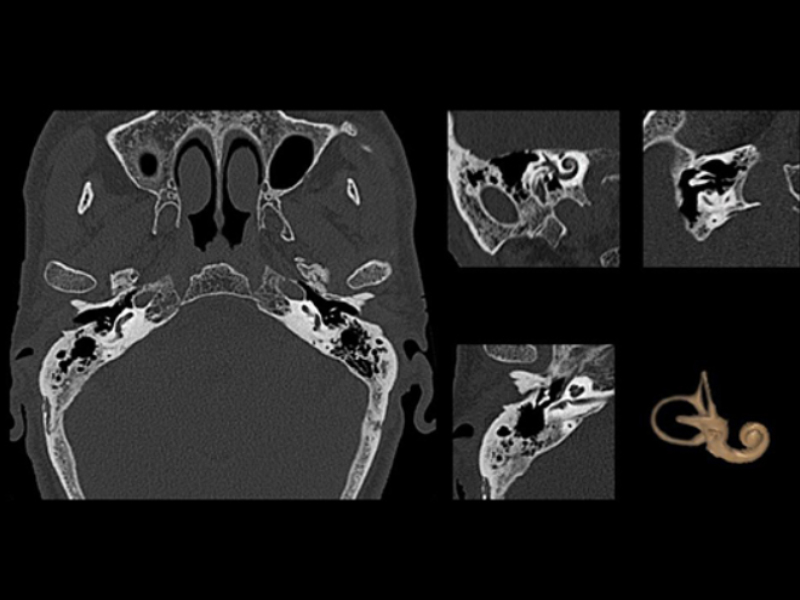

Fine Vascular Structure

Ossicles and Inner Ear